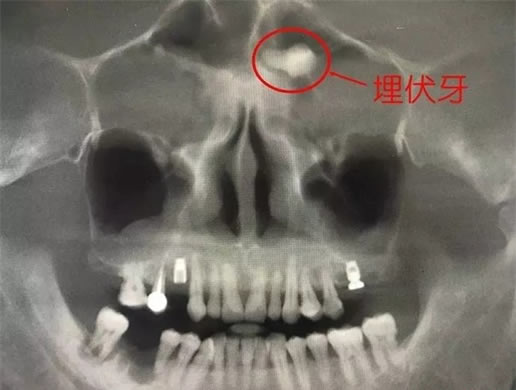

清晰可见“埋伏牙”

通过CBCT,可以看到男子额头竟长了一颗牙,虽然男子的口腔状况“糟糕”,但是他额头上长着的一颗“牙齿”则更是令认惊讶无比,而且该牙齿是导致其多年鼻塞流涕的原因。而在CBCT多种功能帮助下,确定该牙位于左侧筛窦内。利用3D重建切除部分骨,便可看到该牙斜躺着。

医生介绍像这样在其他区域“非法生长”的牙齿,专业上叫做“埋伏牙”。在临时实践中,“埋伏牙”长在上颌窦或牙槽骨等处比较常见,而像这位患者那样长在眉间正中位置的极为罕见。面对此状况,医生立即通知相关科室会诊,着手解决困扰这名患者多年的疾患。